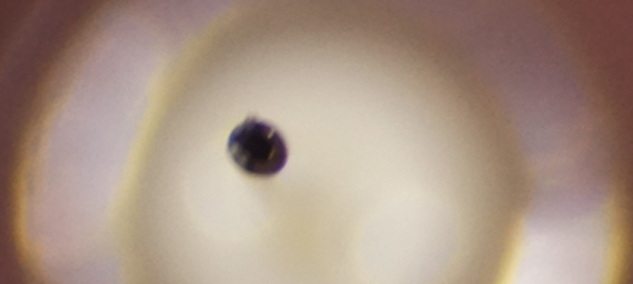

注射針の拡大写真

外径は33Gでは0.26mmでしたが35Gでは0.23mmとなっております。内径は0.11mmと、33G、35G両方変わらないのです。

外径が細くなったからといって注入圧が強くなったりということはないのです。

また、35Gは9°という鋭角な刃面加工と、シリコンコーティングにより痛みの少ない注射が

可能です。

刺通抵抗値は0.445から0.375と15%以上も低下しているようなので、その点も痛みを感じにくくなる点です。